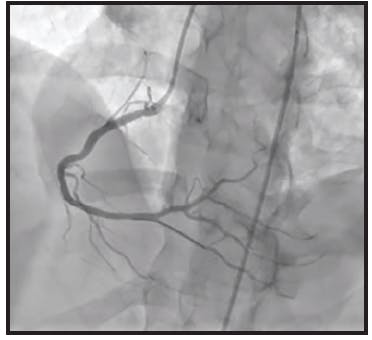

The initial angiogram confirmed an occlusion with extensive thrombus burden of a dominant left circumflex artery and TIMI 0 flow (Figure 1). Power aspiration with CAT RX and Penumbra ENGINE was started after wiring the dominant left circumflex artery. After one pass with CAT RX, the initial occlusion was removed. A second angiogram showed extensive clot burden spread across multiple branches (Figure 2). Each vessel was wired sequentially, delivering power aspiration via CAT RX to the site of each thrombus. A final angiogram revealed complete reperfusion to the dominant left circumflex artery and branches, with TIMI 3 flow (Figure 3).